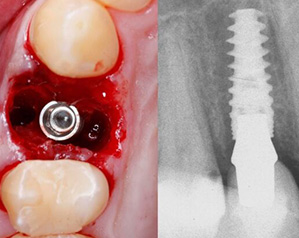

瑞典Nobel是全球第一大种植体生成厂商,由现代种植牙之父Branemark教授合伙创立,其系统可分为骨水平和软组织水平,广泛适用于不同的骨质类型,几乎能解决所有的适应症,是深圳博爱曙光口腔数字化种植战略联盟中的重要合作伙伴,其中,Replace® CC更被广泛运用于针对所有适应症的美学解决方案中。

广泛适用各类缺牙症状,不管是松质骨、拔牙窝还是前牙美观区,都能依赖其独特植体设计实现即刻种植和即刻负重。

要求严苛时,Active逐级扩张的锥形主体、双钻刃的尖端可实现较小骨切割,保持高稳定性;反锥形冠状和内置平台转移设计,实现臻美效果。

1、高初期稳定性

独特设计让骨条件不佳种牙成为现实,面对松质骨或新鲜的拔牙窝也有高初期稳定性,轻松即拔即种、即刻种植,减少骨量需求,为患者节省骨粉费用。

在NobelActive®植入后的愈合过程,仅发生轻微的边缘骨改建,随后骨水平逐渐稳定。

NobelActive®在即刻拔牙种植也有出色的表现,在2-3年随访病例中,平均种植成功率95.7-100%,骨挤压及可改变方向能力,在All-on-4有很好的临床表现。